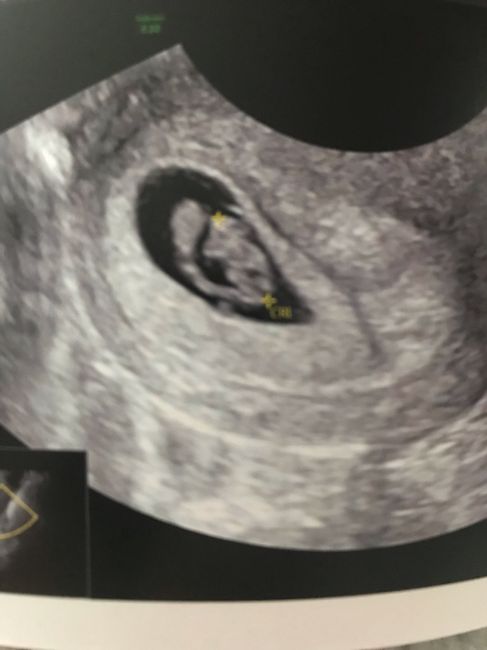

Ciaooo qualcuna ha sentito parlare del metodo Ramzi? A voi ci ha azzeccato o ha sbagliato? Vi metto una foto dell’eco interna a 7+3 “dovrebbe” essere maschio secondo la teoria o sbaglio io a vedere? Altra domandina: l’11 ho fatto il dna fetale (con...